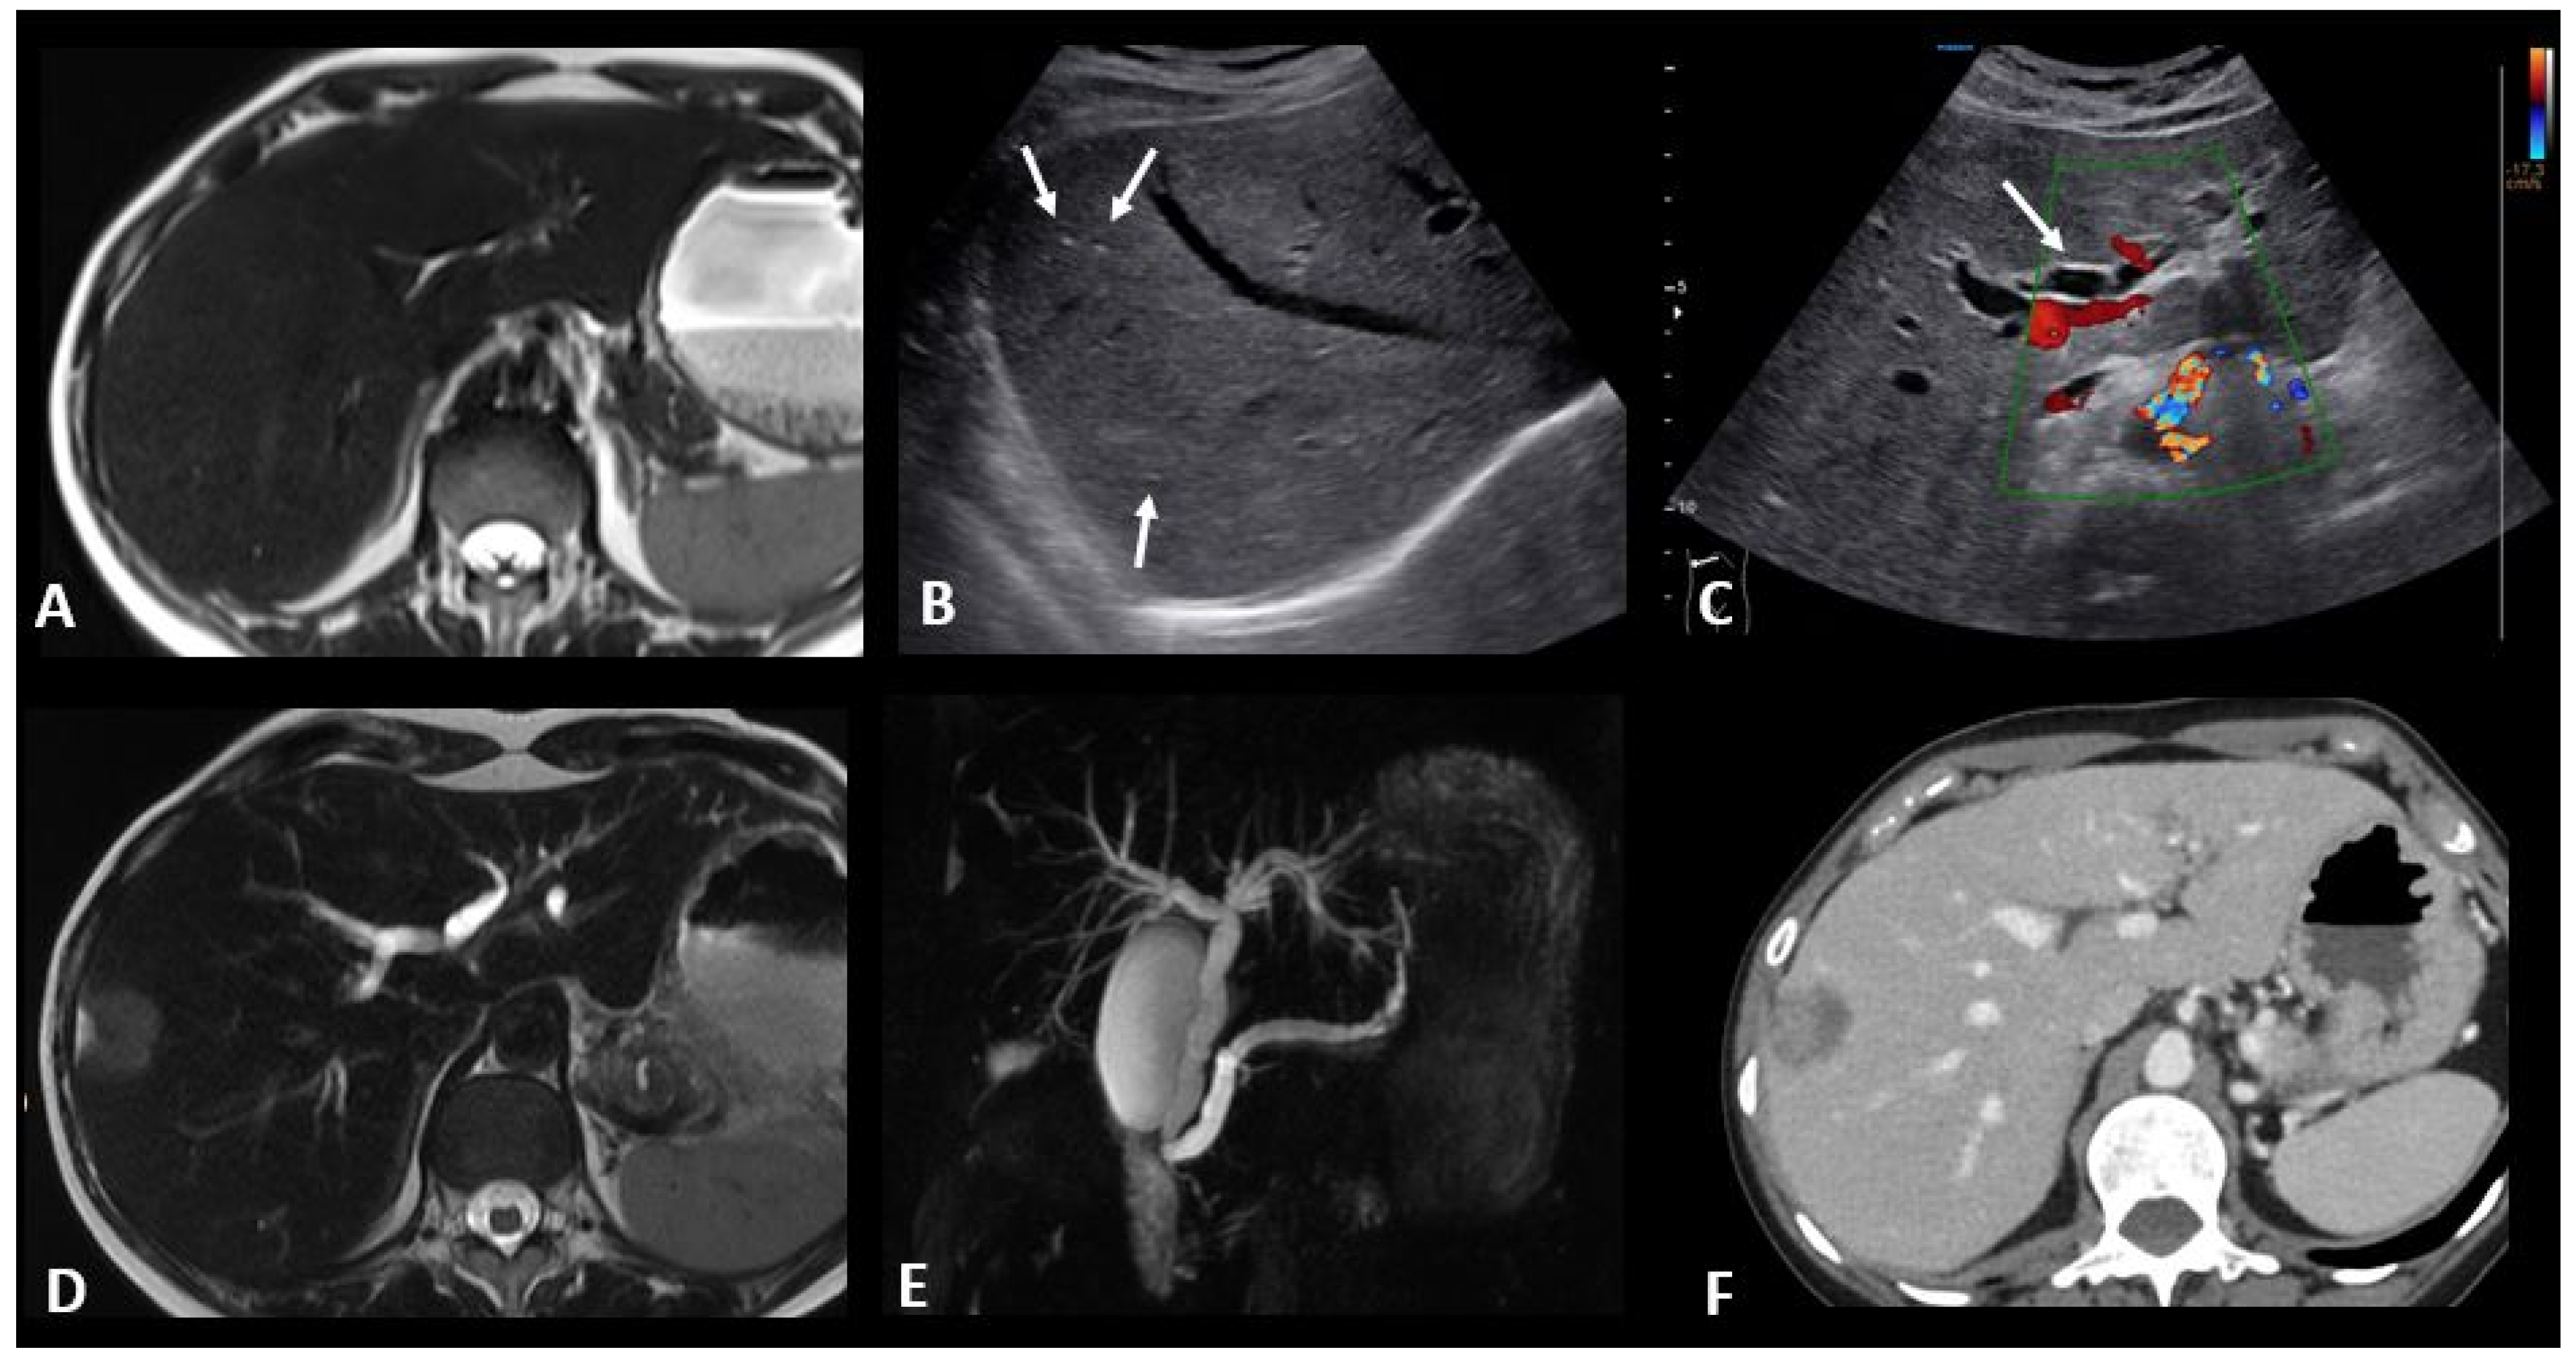

2.4.4. Ir-Cholangitis

- Pi, B.; Wang, J.; Tong, Y.; Yang, Q.; Lv, F.; Yu, Y. Immune-related cholangitis induced by immune checkpoint inhibitors: A systematic review of clinical features and management. Eur. J. Gastroenterol. Hepatol. 2021, 33 (Suppl. S1), e858–e867. [Google Scholar] [CrossRef]